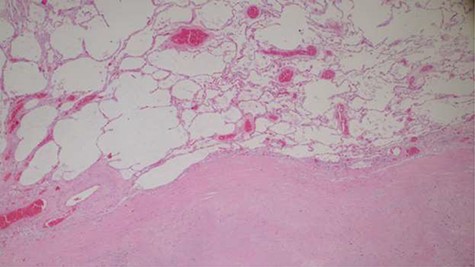

Histopathology analysis of the lung specimens revealed mixed chronic inflammatory infiltrates associated with pulmonary vascular thrombosis and areas of extensive necrosis (Figs 3 and 4). Bowel tissue sections revealed severe ischemic necrosis and mesenteric vessel thrombosis (Fig. 5). Thus, the primary causes of death were ruled to be ischemic colitis and pulmonary thrombosis due to COVID-19. The underlying disease conditions contributing to the cause of death being hypertensive heart disease, diabetes mellitus and septicemia.

Histopathology of lung tissue showing vascular thrombosis and extensive fibrosis and necrosis (hematoxylin and eosin ×40).